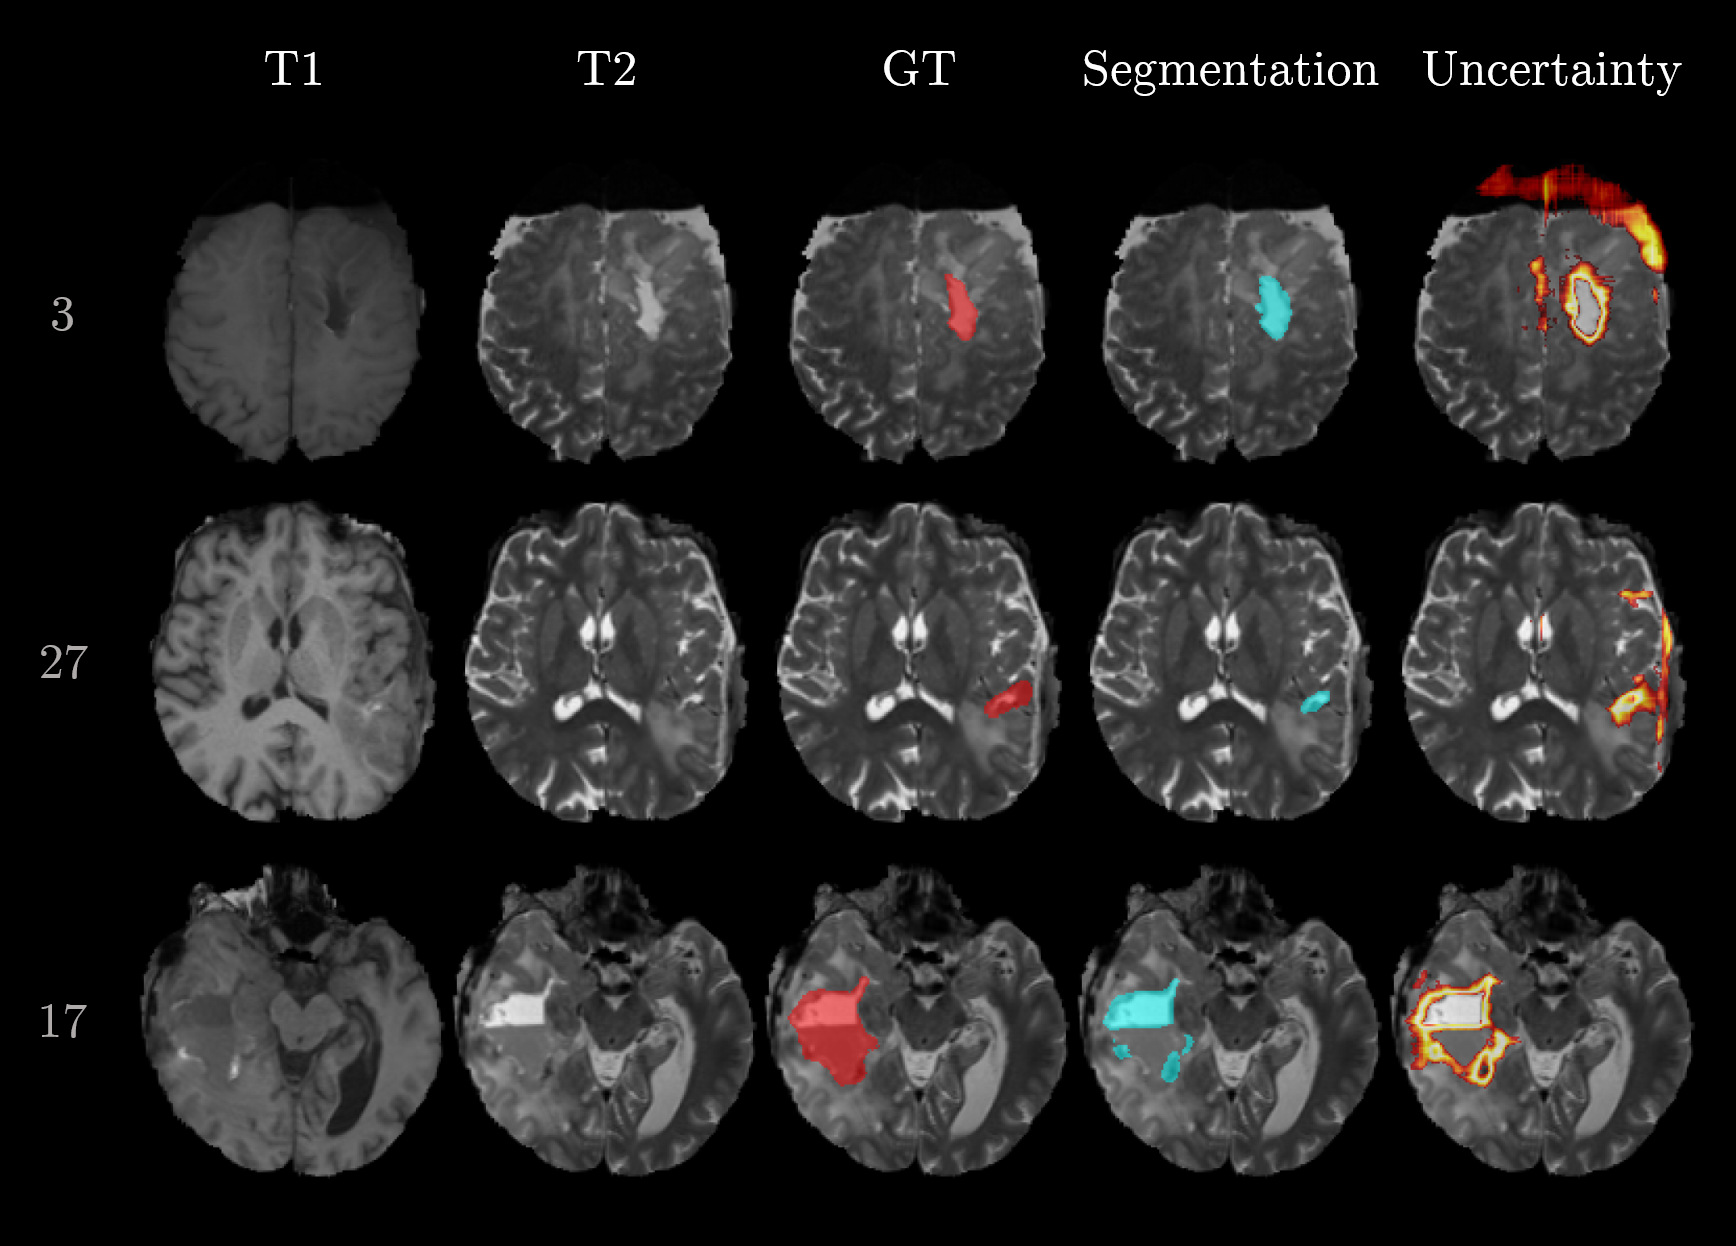

In addition to the qualitative examples in Figure 3, Figure 5 focuses on examples situated in the false positives quadrant (sample 3 and 17) and false negatives quadrant (sample 17). The massive brain shift of sample 3 (top row in Figure 5) does not cause the segmentation to fail but is resulting in an increased uncertainty. Likewise, the uncertainty is increased at the meninges and subarachnoid space for sample 27. Both cases lead to large doubt scores because of the high uncertainties located far away from the segmented cavity. In contrast, sample 17 does mainly show uncertainty around the erroneous segmentation which leads to a small doubt score.